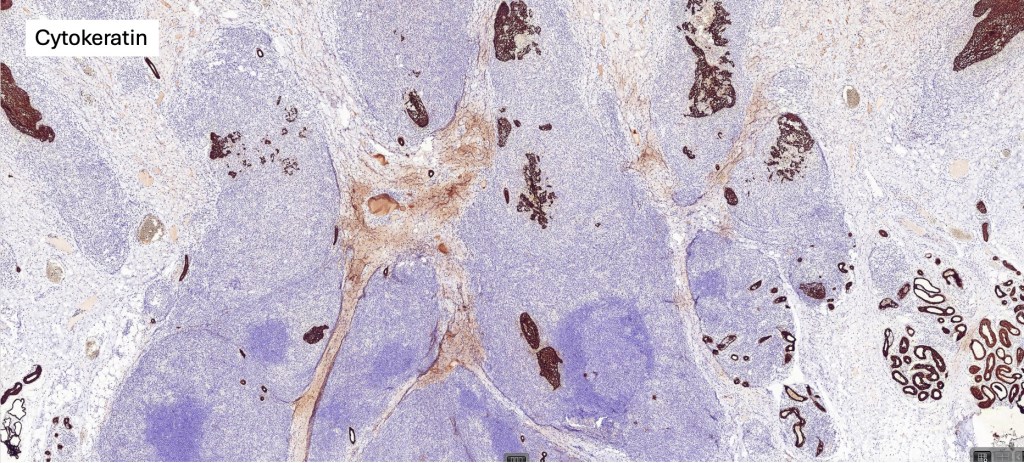

Histological features

•Follicular infiltration by atypical lymphocytes & Sézary cells

•+/- basaloid follicular hyperplasia